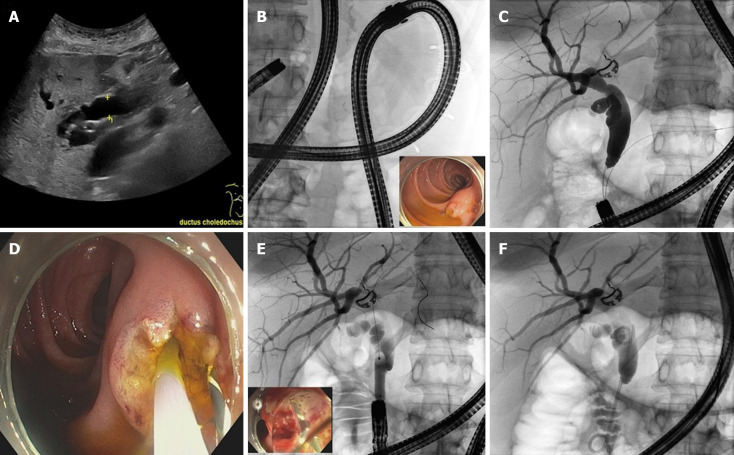

Background: In postsurgical upper gastrointestinal anatomy, motorized spiral enteroscopy (MSE) assisted endoscopic retrograde cholangiopancreaticography (ERCP) was shown feasible and has the advantage that standard ERCP instruments can be used. Therefore, MSE-ERCP appears to be the optimal solution for postsurgical patients, especially with Roux-en-Y anatomy.

Aim: To show feasibility and safety of MSE-ERCP in patients with Roux-en-Y anatomy.

Methods: We retrospectively analyzed all consecutive MSE-ERCP procedures in patients with Roux-en-Y anatomy between September 2021 and May 2023 in an endoscopic tertiary referral center.

Results: We identified 26 MSE-ERCPs: (1) 18 MSE-ERCPs in 13 patients with Roux-en-Y anatomy after liver transplantation (n = 11) or gastrectomy (n = 2); and (2) Another 8 MSE-ERCP interventions in 5 patients with very long Roux-en-Y situation after gastric bypass. Overall success of reaching the biliary entry was 88% and further interventions were successful in 83% of patients. In very long alimentary limb situations, success of reaching the biliary entry was not-significantly lower compared to "standard" Roux-en-Y (75% vs 94%, P = 0.215). ERCP-interventions were not-significantly less successful in patients with native papilla compared to hepaticojejunostomy (63% vs 93%, P = 0.103). Mean intervention time was 105 minutes. Intervention times were longer in very long limb situations (133 minutes vs 91 minutes; P = 0.032). Overall, we observed three adverse events (n = 1 caused by enteroscopy, n = 1 caused by the biliary intervention, n = 1 unrelated to the procedure). In 15/26 cases (58%) MSE-ERCP was carried out on an outpatient basis.

Conclusion: MSE-ERCP has been a promising technique for patients with Roux-en-Y reconstruction requiring biliary interventions. However, MSE was recently withdrawn from the market due to severe safety concerns, which were not observed in this study.